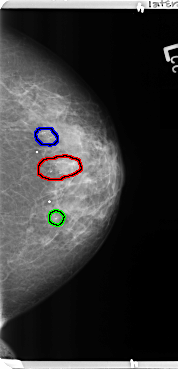

FILE: B_3364_1.LEFT_CC.OVERLAY

TOTAL_ABNORMALITIES 3

ABNORMALITY 1

LESION_TYPE CALCIFICATION TYPE PLEOMORPHIC DISTRIBUTION CLUSTERED-SEGMENTAL

ASSESSMENT 4

SUBTLETY 4

PATHOLOGY BENIGN

TOTAL_OUTLINES 1

BOUNDARY

ABNORMALITY 2

ABNORMALITY 3